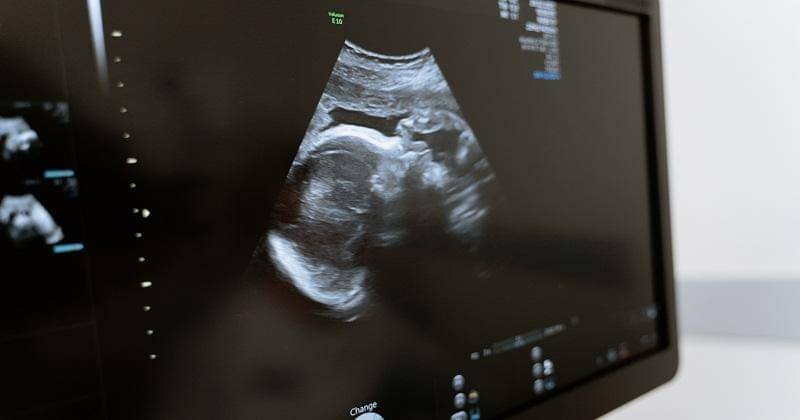

Prosedur amnioinfusi dilakukan dengan bantuan USG. Dokter akan mencari celah kecil antara rahim dan janin untuk memasukan cairan infus ke dalam rahim.

Amnioinfusi dilakukan dengan sangat hati-hati agar jarum tidak mengenai dan melukai janin. Setelah cairan ditambah, bisa dilihat melalui layar jumlah cairan dan janin pun bisa bergerak dengan lebih leluasa, Ma.